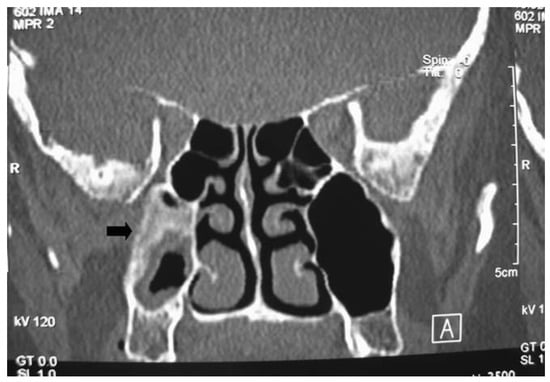

3. Imaging

- Yousuf, K.; Wright, E.D. Site of attachment of inverted papilloma predicted by CT findings of osteitis. Am. J. Rhinol. 2007, 21, 32–36. [Google Scholar] [CrossRef]

- Lee, D.K.; Chung, S.K.; Dhong, H.J.; Kim, H.Y.; Kim, H.J.; Bok, K.H. Focal hyperostosis on CT of sinonasal inverted papilloma as a predictor of tumor origin. AJNR Am. J. Neuroradiol. 2007, 28, 618–621. [Google Scholar]

- Bhalla, R.K.; Wright, E.D. Predicting the site of attachment of sinonasal inverted papilloma. Rhinology 2009, 47, 345–348. [Google Scholar] [CrossRef]